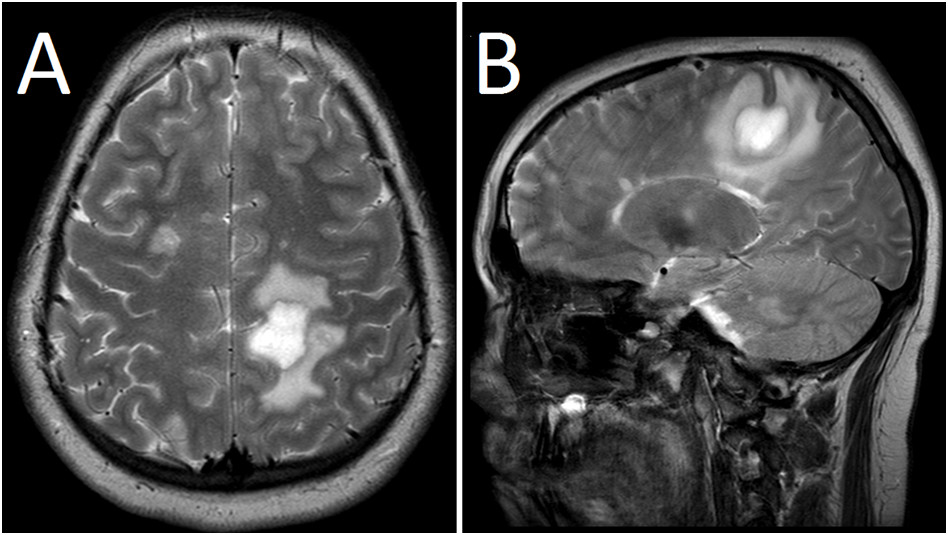

MR głowy wykonano u 12-letniego chorego (A - przekrój poprzeczny, B - przekrój strzałkowy). Wskaż najbardziej prawdopodobne rozpoznanie: